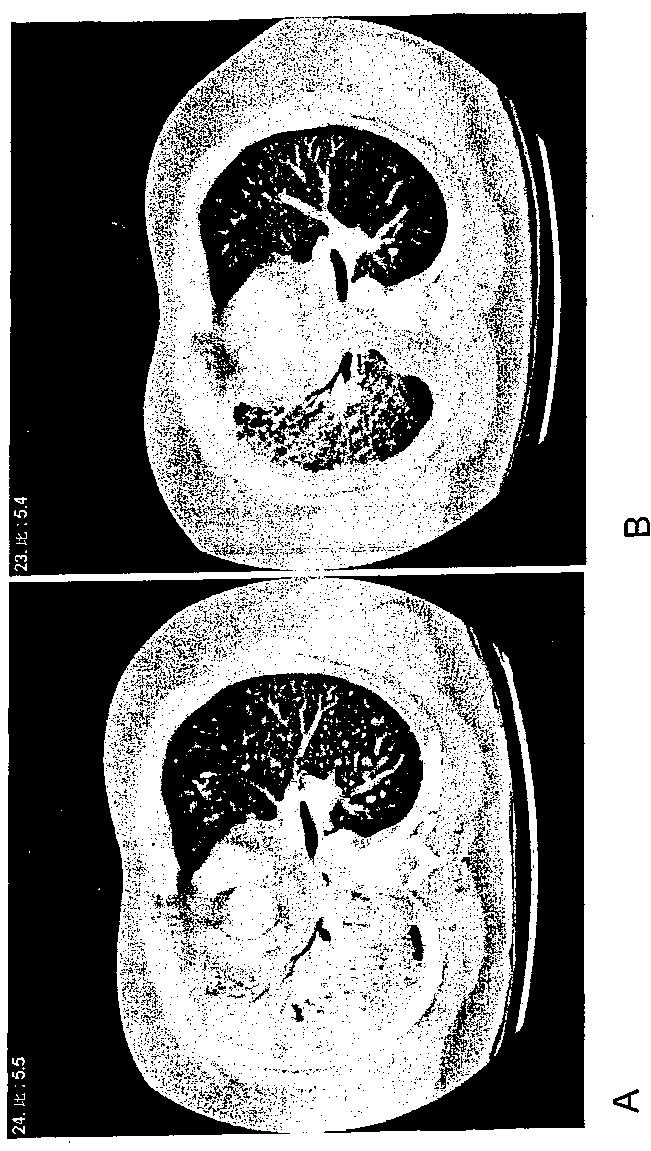

上皮細胞成長因子受容体ターゲティング治療に対する癌の応答性を決定する方法